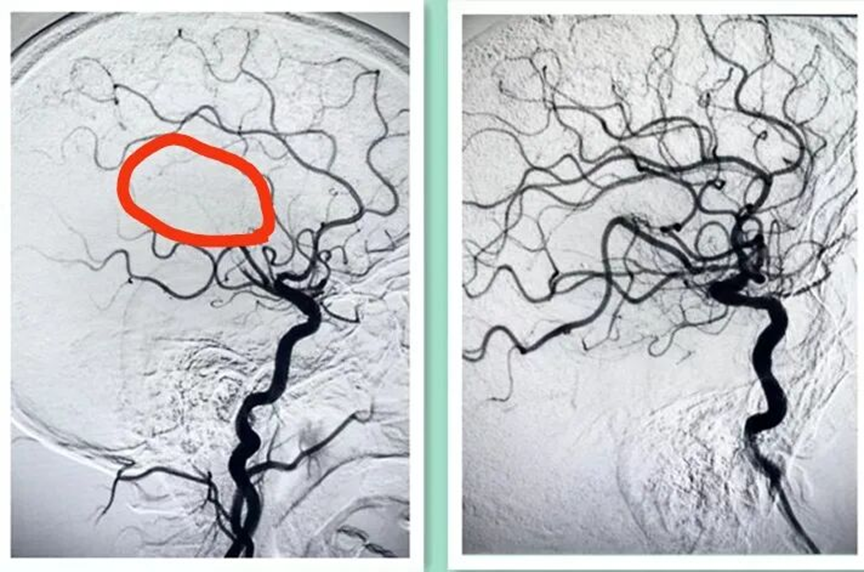

神经内科武钟毅主任及孙玉琴主治医师行脑血管造影,术中发现患者右侧大脑中动脉上干闭塞,采用SWIM技术进行大脑中动脉取栓术,使右侧大脑中动脉血流达到3级再通。

右侧大脑中动脉上干闭塞( 术前 )

右侧大脑中动脉上干闭塞( 术后 )